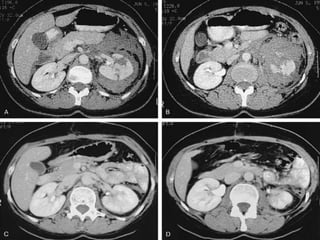

Nonoperative Management

98% of renal injuries can be managed nonoperatively

A hemodynamically stable patient with blunt renal injury and well

staged by CT (Grade I- IV) can usually be managed without renal

exploration

– Grade IV and V injuries more often require surgical exploration

– Even Grade (IV-V) can be managed without renal operation if they are

carefully staged and selected

Penetrating trauma from gunshot or stab wounds to the kidney can be

managed nonoperatively if carefully staged with CT

– 55% of renal stab wounds and 24% of gunshot wounds were appropriately

managed nonoperatively in carefully selected patients with well-staged

injuries